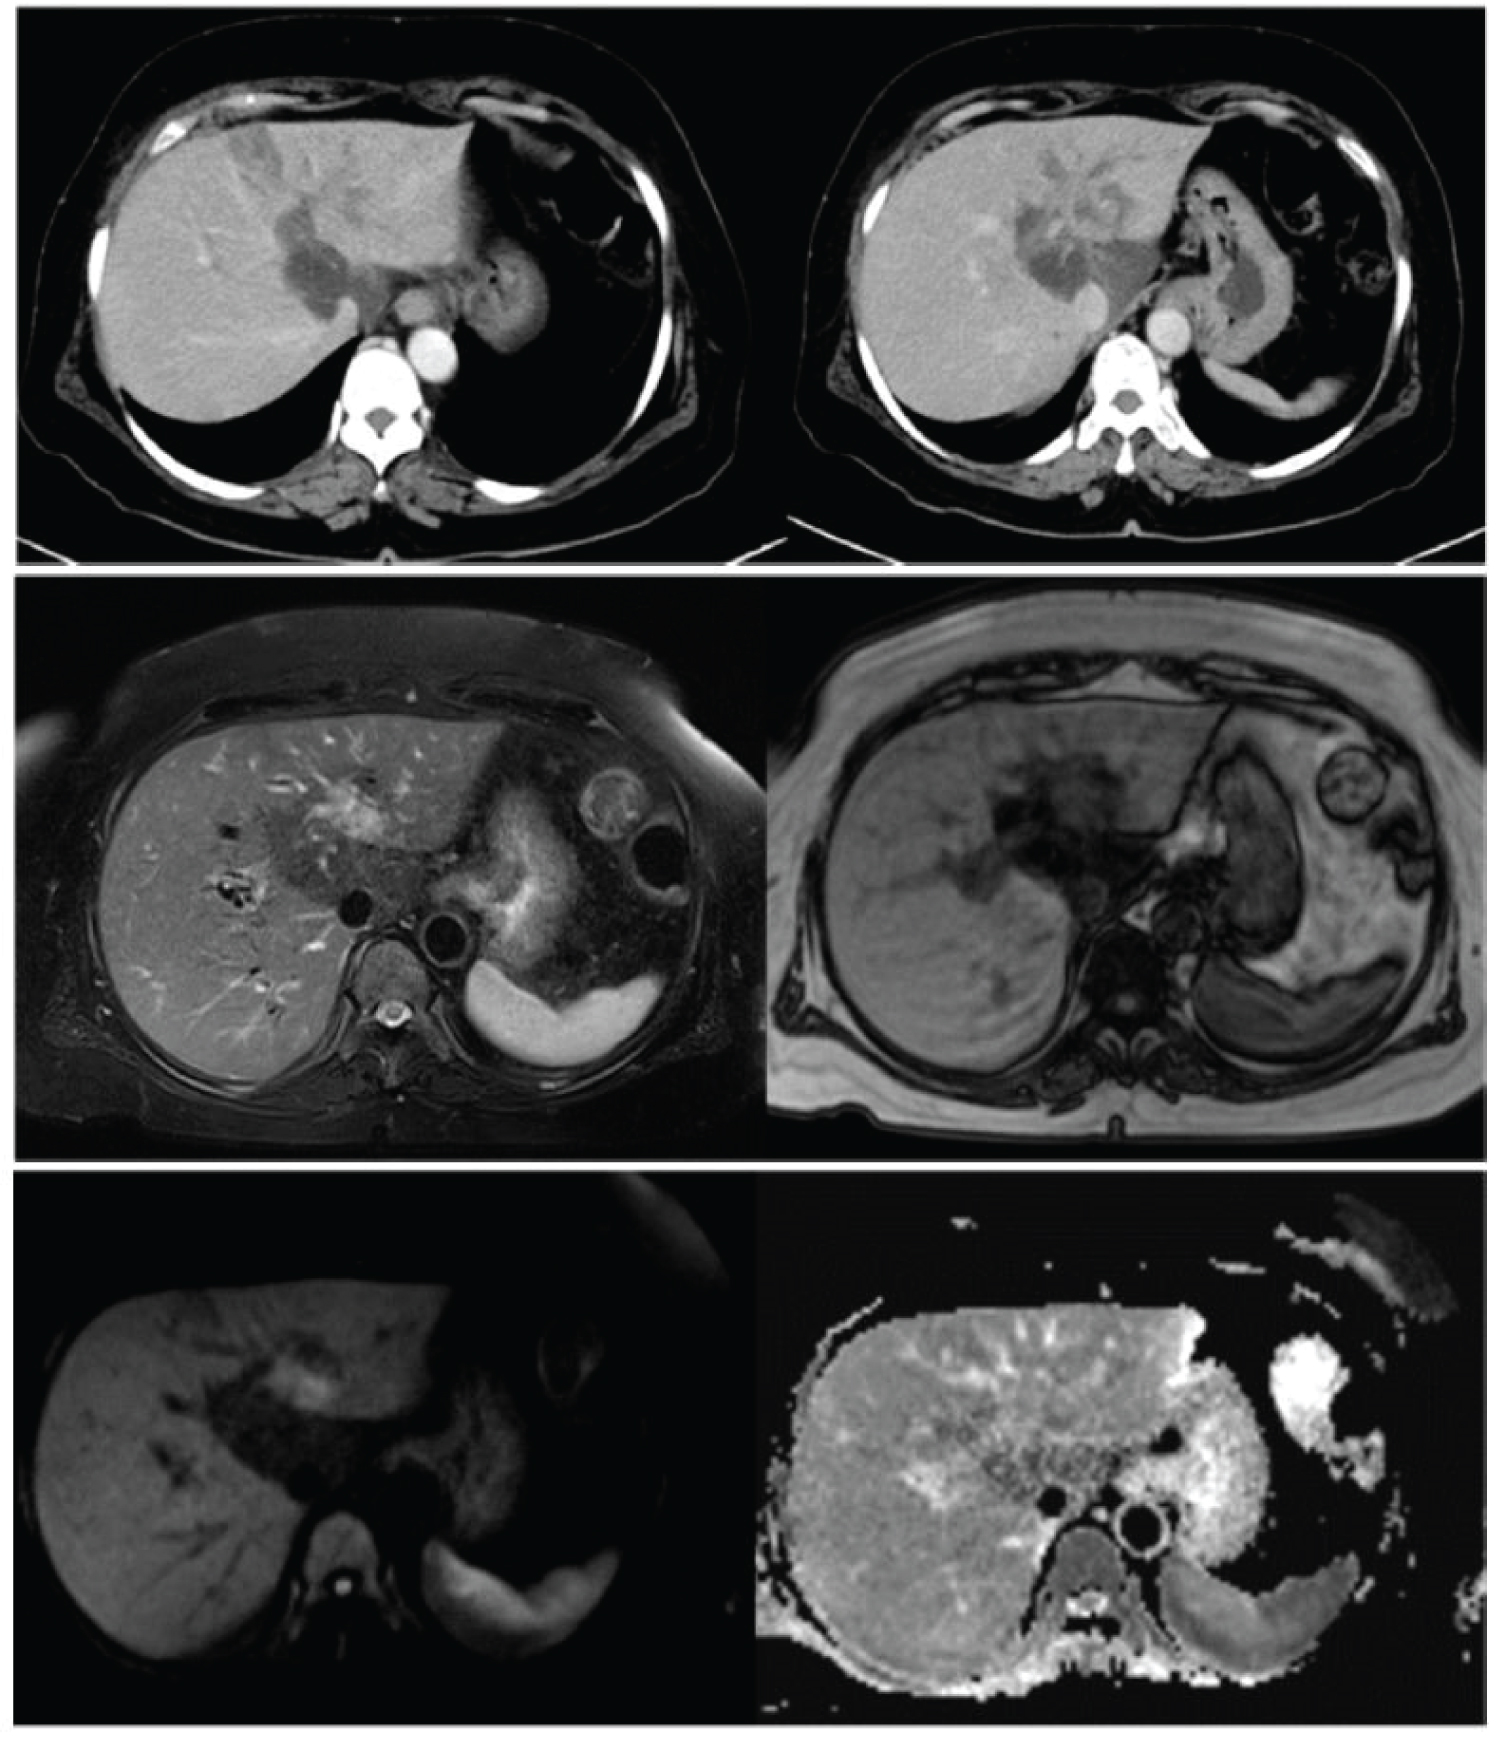

Our patient is an elderly female who presented with features of obstructive jaundice and upper abdominal pain for one month. Lab parameters were suggestive of obstructive pattern of jaundice and CECT is taken to rule out malignancy. CECT shows ill-defined heterogeneously hypo-enhancing lesion seen involving the medial aspects of segments 2/3 with upstream biliary radicle dilatation in the segments 2 & 3. In MRI, lesion appears T2 hyperintense, T1 hypointense with no diffusion restriction (Figure 4). Since the imaging findings were not very typical of cholangiocarcinoma, other possibilities were considered and screened for serum IG G4 levels which came out to be in high range. Then then patient was started on steroids and patient improved clinically with resolution of jaundice.

Figure 4: Inflammatory pseudotumor. (a,b) CECT axial sections show an ill-defined heterogeneously hypo-enhancing lesion seen involving the medial aspects of segments 2/3 with upstream biliary radicle dilatation in the segments 2 & 3. Geographic fat attenuating area involving caudate lobe and segment 4 of liver; (c,d) MRI T2 FS (a) and T1 out of phase (b) axial sections shows ill defined T2 FS hyperintense and T1 hypointense lesion in the medial aspects of segments 2/3 of liver; (e,f) MRI DWI (e) and ADC (f) axial sections shows ill-defined lesion that appears hyperintense and isointense in the diffusion weighted and ADC images respectively, suggestive diffusion shine through. View Figure 4